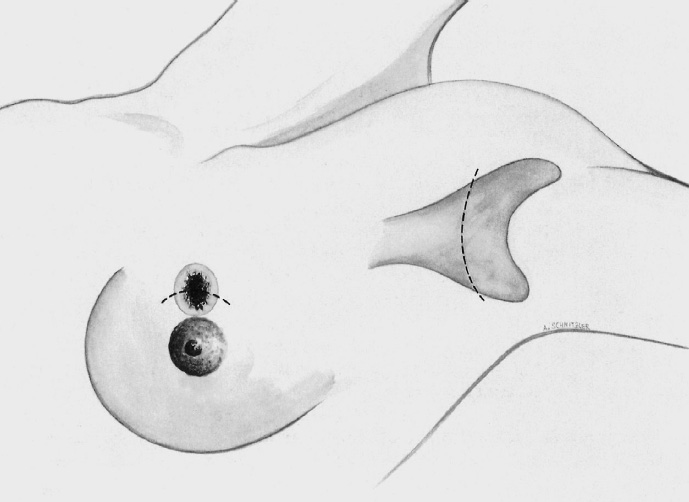

The basic decision on whether to use a complex oncoplastic technique is made when the skin is marked preoperatively, with the patient standing or sitting upright. Many surgeons successfully combine the B-plasty incision with periareolar de-epithelialization and excision of a straight or curved ellipse of peripheral skin (Chapter 1.3). When marking the periareolar deepithelialization pattern, an eccentric incision may be necessary to adjust the repositioning of the nipple–areola complex to the anticipated volume displacement.

The skin is incised superficially along the preoperative mark, initially with a scalpel. Many surgeons then proceed using electrocautery needle or scissors.

The periareolar skin is de-epithelialized. Here, too, there are various options. A strip of the most superficial skin layer can be excised with dissecting scissors applied flat or with a scalpel. It is important not to leave behind any surface containing squamous epithelium, but on the other hand the dermis and the important vascular layer beneath it must not be injured. The purpose of periareolar de-epithelialization is to recenter the nipple–areola complex and also to tailor excess skin to the new breast shape following extensive tumor resection.

Segmental excision of the area containing the tumor with resection margins as wide as possible to meet oncological criteria. Oncoplastic techniques should be used to achieve maximal oncological safety and avoid subsequent further resection.